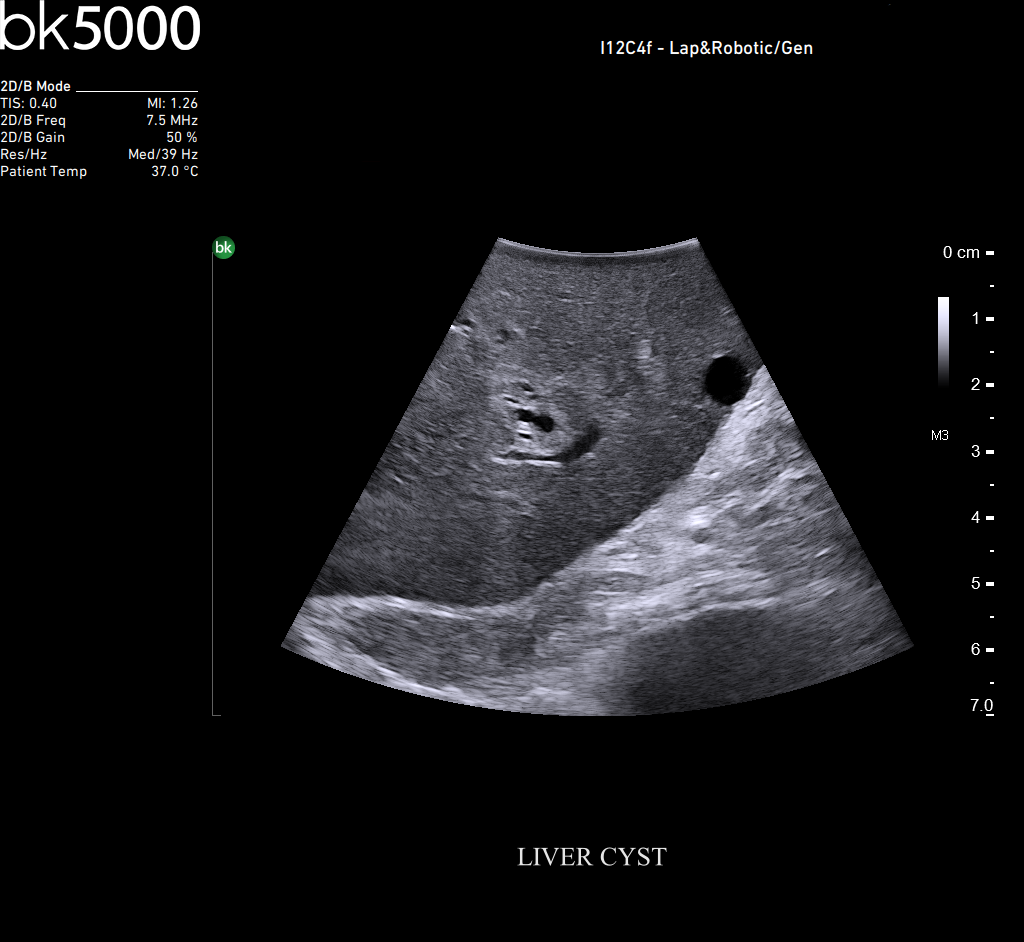

Ultrasound can advance intraoperative surgical procedures by helping you navigate and identify lesions and anatomical structures in real-time. This is particularly important as the data obtained from a preoperative CT or MRI scan can be outdated at the time of surgery.

The bk5000 surgical system provides the highest quality images that allow you to clearly see the margins of a lesion and to determine the best course of action. Using advanced graphics processing technology, this powerful system provides immediate, auto-optimized images that allow you to see the information you need, faster.